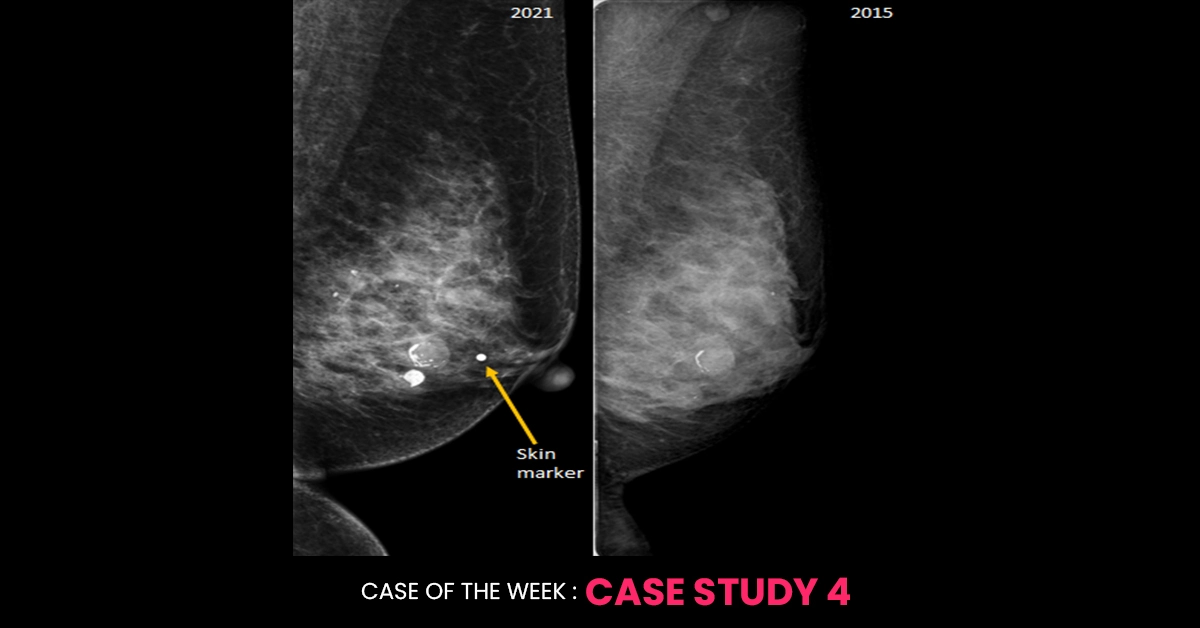

A 56-year-old woman presented with a new palpable lump in the left breast. Left MLO mammogram from the current study as well as a study from 4 years ago are provided. What is your BIRADS?

Underneath the area of the palpable lump in the left breast, a circumscribed isodense mass is seen with internal coarse calcifications; most likely an involuting fibroadenoma. It was also seen in the 2015 study with peripheral calcification. Though the patient may be now able to feel the same lesion (may be due to post-menopausal changes in the breast or maybe the patient has started consciously performing breast self-examination etc.) at the same time a new underlying more sinister cause that is obscured by dense breast tissue on mammogram is not ruled out,  she deserves further evaluation with cone compression view/ Tomosynthesis and ultrasound for the region of new palpable concern. That is why this mammogram should be reported as BI-RADS 0 and the patient should be further evaluated.  If the further workup confirms the palpable lump to correlate with this involuting fibroadenoma and no other suspicious feature is identified, then she can be discharged with final BI-RADS 2 after the complete work up.